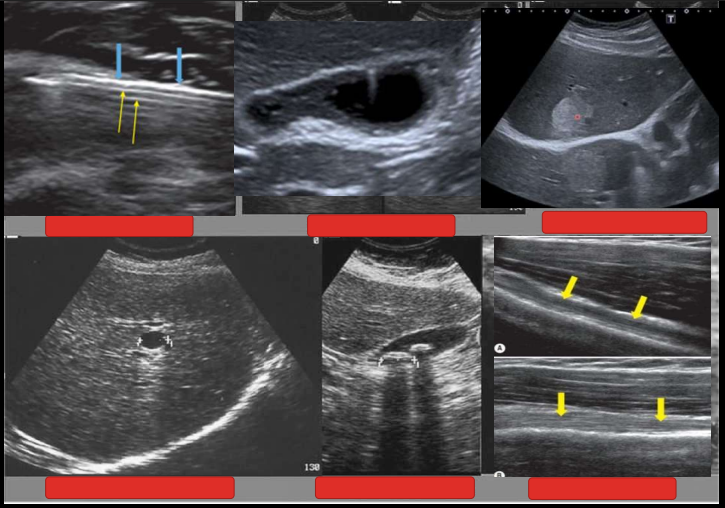

<p>Nomenclatura de la flehca azul y amarilla</p>

Nomenclatura de la flehca azul y amarilla

Hiperecogénico o Hiperecoico

Anecoico

<p>Nomenclatura del circulo con respecto de su entorno</p>

Nomenclatura del circulo con respecto de su entorno

1. Isoecogénico

2. Heterogéneo

3. Hiperecogénico

4. Hiperecogénico + sombra acústica posterior

5. Anecoico + Refuerzo posterior